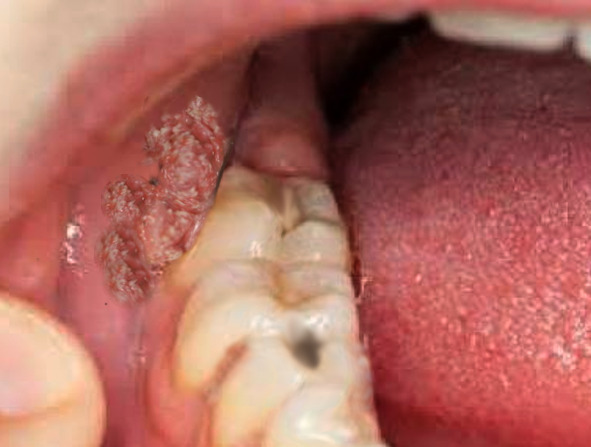

모양은 '컬리 플라워'같은 사마귀가 소음순, 대음순, 항문주변, 질 입구, 질 안, 자궁경부, 항문, 음경까지 발생할 수 있어요. 피부 색의 유두 모양의 돌기들이 옹기종기 모여 발생하게 되요. 발견이 어려운 위치에 있는 경우는 이렇게 산부인과 검진하다가 발견하게 되죠.

콘딜로마는 대체적으로 항문생식기 부분에 많이 생기지만, 때로는 구강에서 발견되기도 합니다. 어쨌든, 항문생식기에 생긴 경우 항문 생식기 부분에 성적 접촉이 있었다는 것을 알 수 있고, 구강에서도 보통 오럴섹스를 하면서 전파되어 발생할 수 있습니다.

병변은 일반적으로 여러 군데에서 발견될 수 있고 이들이 결국 모여서 큰 덩어리로 합쳐져 큰 병변으로 진행되기도 합니다. 그러나 단독으로 하나만 딱 보이는 경우도 있어요. 구강 콘딜로마는 종종 혀나 입술에서 발견됩니다. 항문생식기 부분에서는 음경, 대음순, 질, 자궁경부, 때로는 복강, 그리고 항문에 생길 수 있어요. 생긴 모양은, 콘딜로마는 일반적으로 융기되어 있고, 피부 색으로 되어 있으며 작은 돌기들이 모여있는 군집으로 발견됩니다. 앞에 그림에서 보셨듯이 컬리플라워 모양으로 나타나요. 만약 매우 큰 덩어리를 이루는 종양이 항문생식기 부위에 있다면 Buschke-Lowenstein tumor를 고려해야 하는데, 이는 콘딜로마에서 악성 변성이 합병된 상태입니다. 이런 경우는 드문 경우니 너무 걱정하시지는 마세요. :)